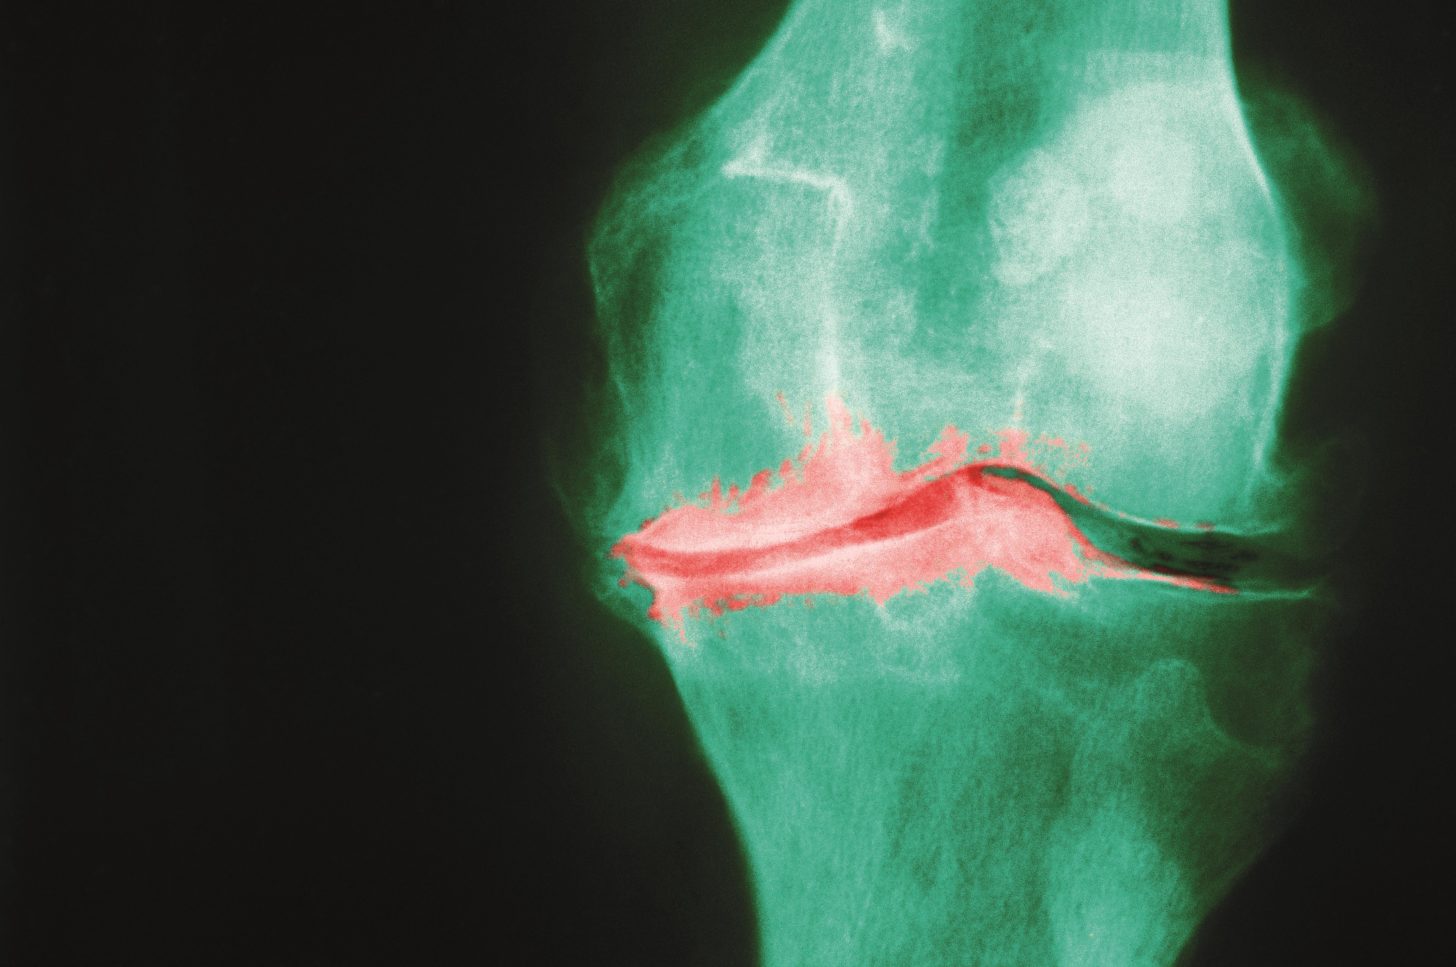

Paracetamol 'not clinically effective' in treating osteoarthritis pain or improving physical